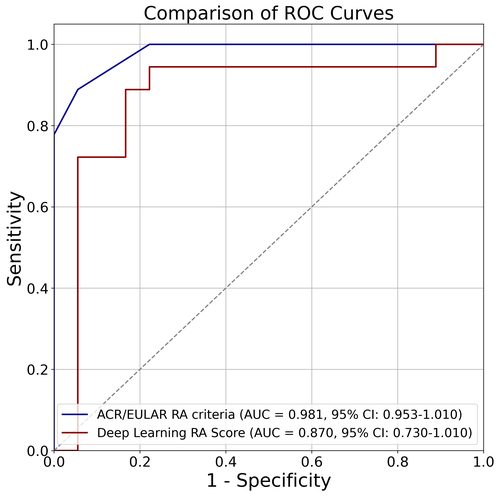

当科では、日常診療から生まれるクリニカルクエスチョンを大切にし、臨床研究へとつなげています。特に力を入れているのが、深層学習(ディープラーニング)を用いた関節リウマチの診断支援システムの開発です。

従来のACR/EULAR分類基準とは異なるアプローチで、臨床データから直接RA診断を支援するスコアリングシステムを構築。そのキャリブレーションとROC解析の結果は、新たな診断支援ツールとしての可能性を示しています。

専攻医もこうした研究プロジェクトに参画でき、学術発表や論文執筆の機会を得ることができます。